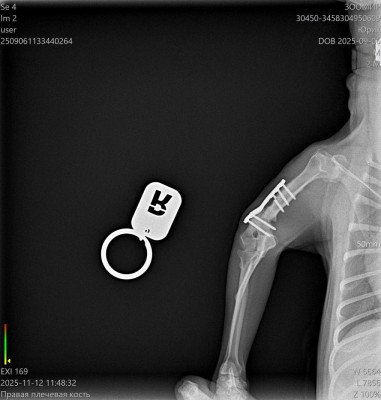

Сделали контрольный рентген - пока мозоли не видно:((((

Теперь через месяц.

Лапой на ровном немного пользуется. Но это за счет пластины.

Рентген